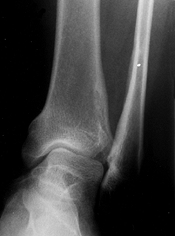

![]() |

|

Figure 180.5. Relative fibular overgrowth in a 13-year-old girl with achondroplasia.